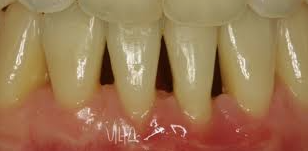

찬물을 마시거나 양치질을 할때 갑자기 이가 시린 증상이 있습니다. 이럴때 시린 부위의 잇몸이 내려앉아 있는 현상을 볼 수 있습니다. 나이가 들어갈수록 잇몸이 내려가게 되고 점차 치아의 뿌리까지 보여질 수 있다고 합니다. 잇몸이 있어야 치아도 버틸수 있습니다. 잇몸 내려앉음 증상의 원인과 치료방법, 예방법에 대해서 알아보도록 하겠습니다.

치과의사 선생님의 이야기를 들어본 결과 내려앉은 잇몸은 다시 올리는건 어려우며 현재를 유지하는 방법이 최선이라고 합니다. 잇몸 내려앉음 치료방법에는 앞서 소개된 원인 중 하나인 치석을 제거하는 방법입니다. 위에 오른쪽 사진을 보시면 스케일링 전/후 인데요. 오른쪽 스케일링 후 사진을 보면 치석을 제거하니 치아 사이사이 비어있는 모습이 보입니다. 이렇듯 치석이 많이 끼게되면 잇몸이 내려앉기 때문에 치석이 많이 끼이기 전에 스케일링을 받는 것이 좋습니다. 스케일링은 1년마다 1번씩 보험처리가 가능하기 때문에 1년에 1번 스케일링을 꾸준히 받아주시는게 좋습니다.